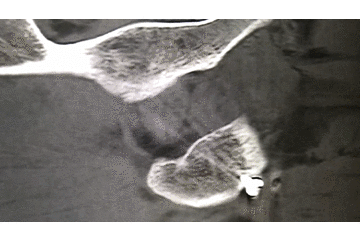

辅助检查:CT 检查提示右侧股骨颈骨皮质不连续,可见透亮骨折线及碎骨片影,断端错位、成角,周围软组织肿胀;右侧髋臼后下缘及左侧耻骨上支骨皮质不连续,断端未见明显错位;右侧髋臼后缘见类圆形稍低密度影,大小约 5*9 mm,边界清楚,边缘见硬化边;右侧髋关节在位,关节间隙未见明显变窄。

初步诊断:右股骨颈骨折(经颈型)